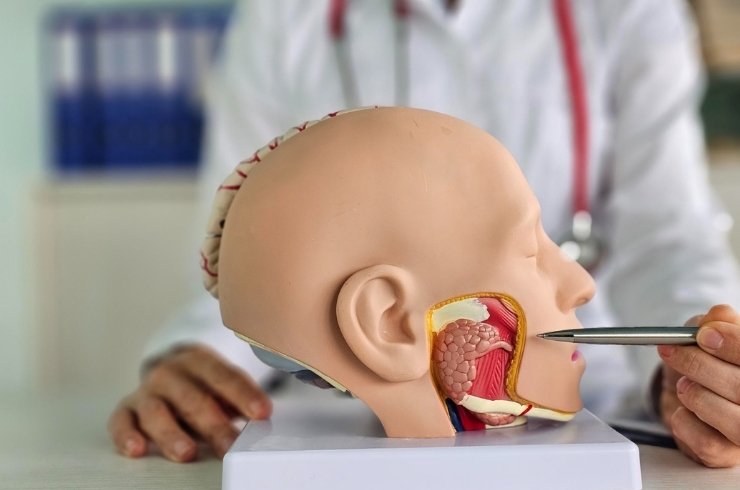

Complete ENT care for allergies, infections, hearing issues, sinus problems, and throat disorders using modern diagnostic methods.